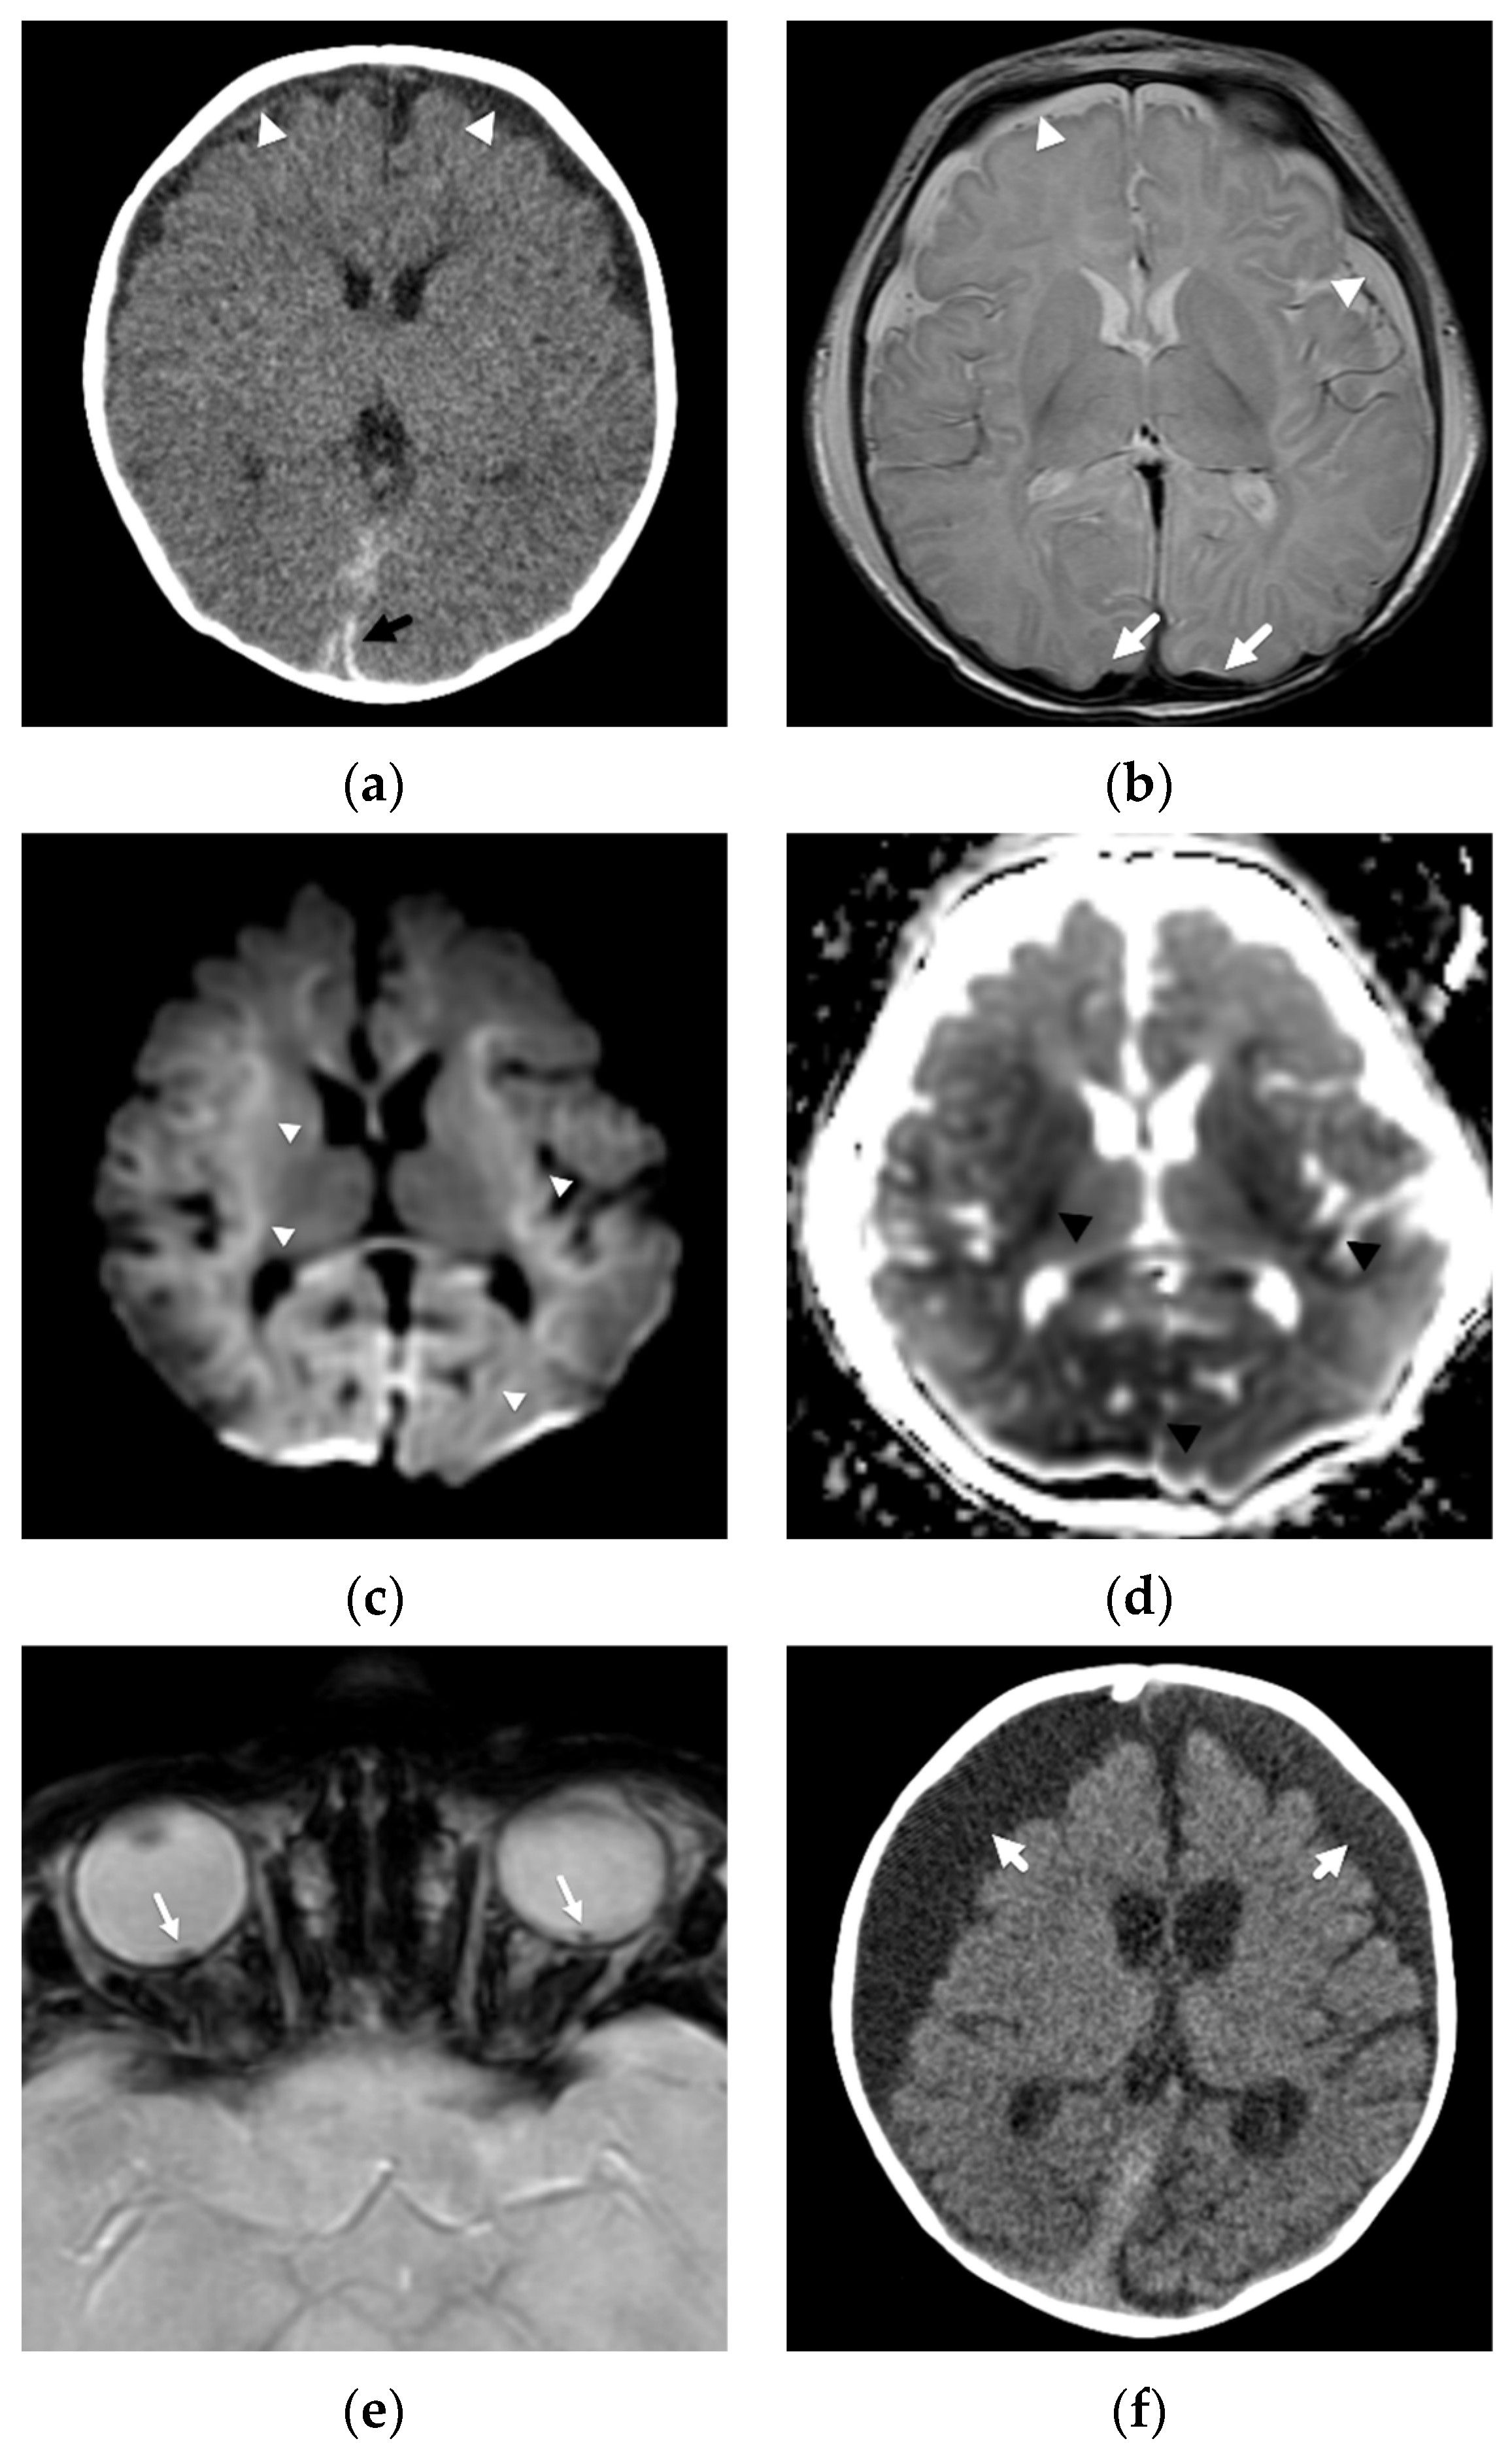

2. Patterns of Diffuse Parenchymal Insults

3. Imaging of Diffuse Insults

4. Focal Parenchymal Insults

5. Imaging Evaluation